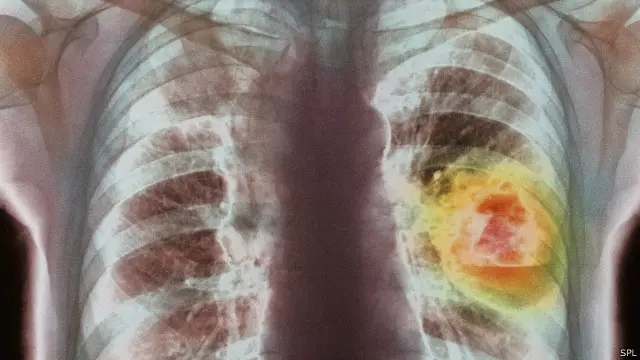

علاج جديد لسرطان الرئة يمثل "علامة فارقة"

ربما يضاعف علاج جديد لسرطان الرئة متوسط العمر المتوقع عند بعض المرضى، حسب ما أظهرت تجربة "فارقة".

ويعد مرض سرطان الرئة من أكثر أنواع السرطان فتكا، إذ يتسبب في موت نحو 1.6 مليون شخص سنويا على مستوى العالم.

ومن الصعب علاج هذا المرض بسبب عدم اكتشافه في وقت مبكر في الغالب، كما أن الكثير من الأشخاص الذين يعانون أمراضا مرتبطة بالتدخين يكونون غير مؤهلين للخضوع لعمليات جراحية.